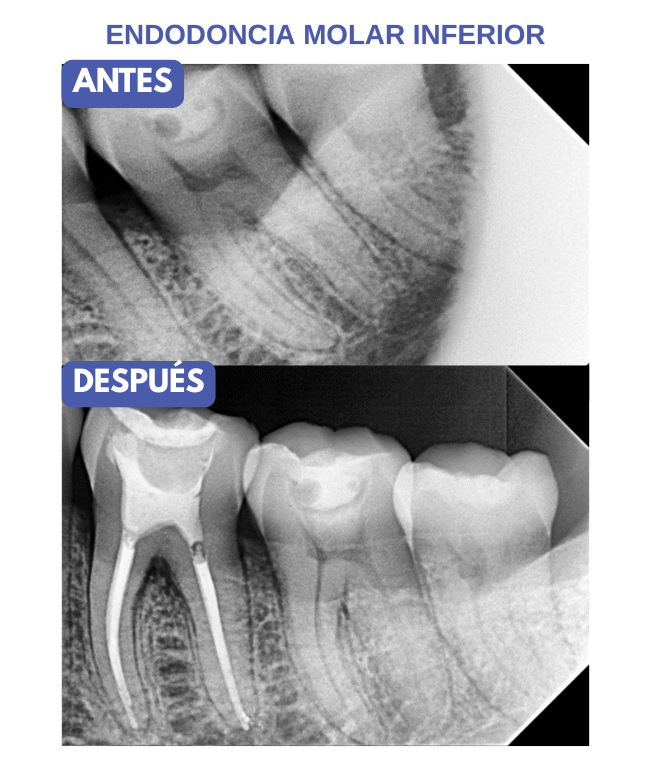

Casos de Endodoncia

En nuestras clínicas realizamos tratamientos de endodoncia con resultados comprobados, devolviendo la salud y funcionalidad a dientes afectados por caries profundas, traumatismos o infecciones. Cada paciente recibe un diagnóstico detallado, planificación personalizada y técnicas modernas que garantizan un tratamiento eficaz y cómodo.

Nuestros casos documentados muestran dientes tratados con éxito, preservando su estructura natural y restaurando la estética y la funcionalidad. Con endodoncia, evitamos extracciones innecesarias y ofrecemos soluciones duraderas que protegen tu sonrisa a largo plazo.